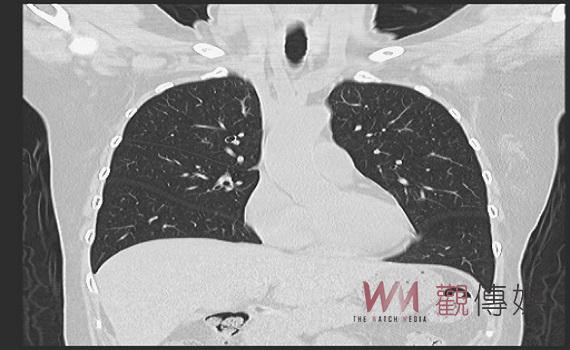

▲肺癌篩檢真的很重要 埔榮員工也受惠。

國健署自去年7月1日起補助肺癌高風險族群每2年1次免費低劑量電腦斷層(LDCT)篩檢,短短半年就揪出160個確診肺癌個案。新診斷的四期(末期)肺癌個案比例更從57.9%下降為109年度的50.1%,減少近8個百分點,對於四期存活率極低的肺癌來說,是難能可貴的一大進步。